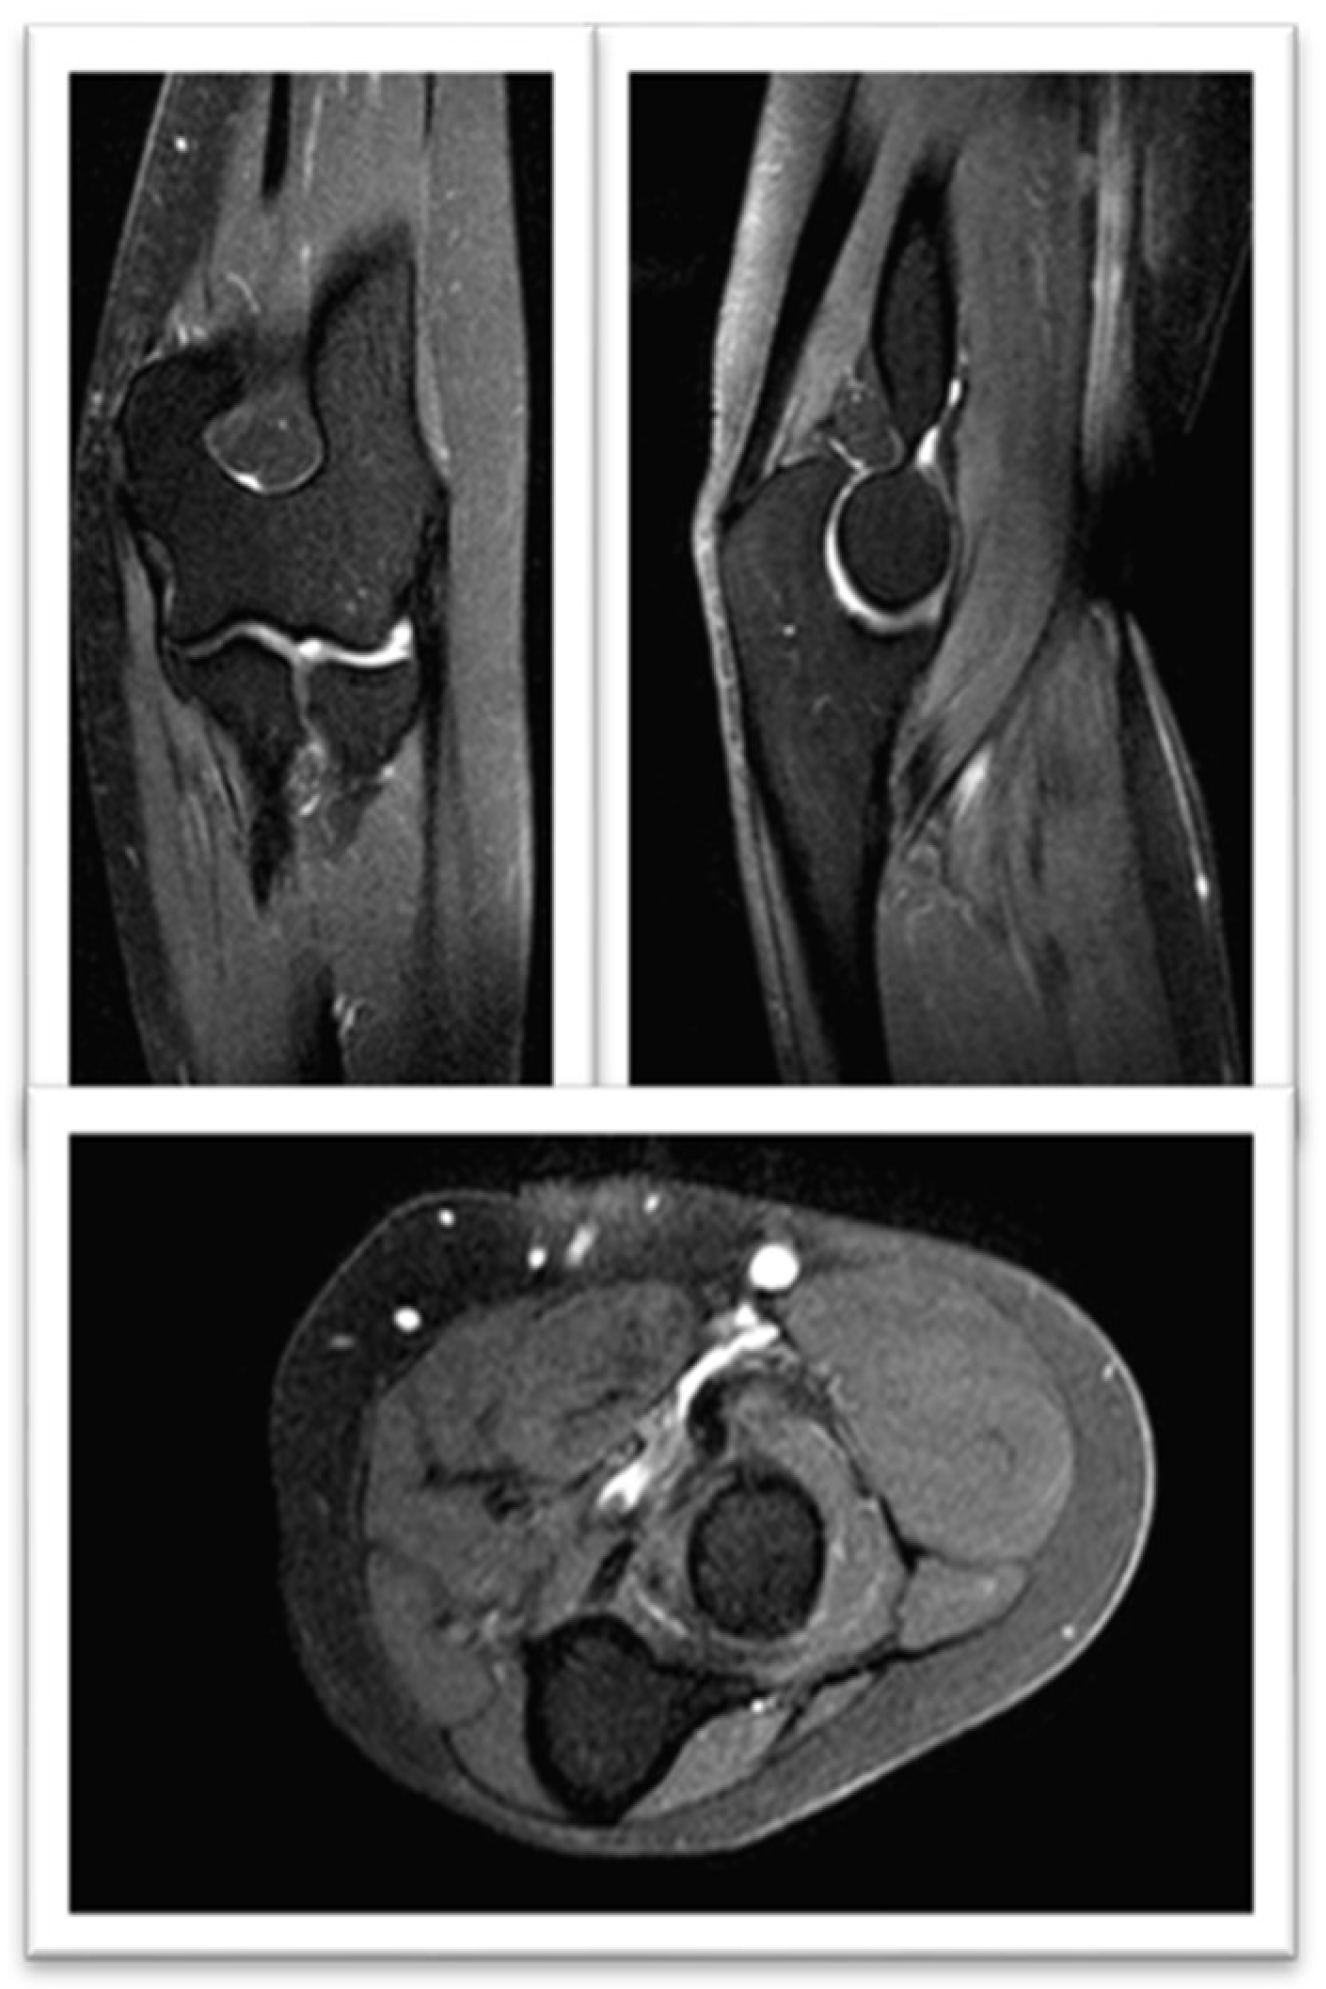

Complementary Test Results: Laboratory analysis: ESR: 80 mm/hr; Hemoglobin: 12.8 g/dL; Urea: 57 mg/dL; Creatinine: 0.93 mg/dL; GOT (AST): 16 U/L; GPT (ALT): 10 U/L; GGT: 13 U/L; CRP: 1.8 mg/dL; CPK: 563 U/L; Aldolase: 3.6 U/L (<7.6). Imaging studies: Ultrasound: Altered signal in the gluteus maximus and medius muscles. MRI: Signal abnormalities with enhancement involving the gluteus maximus and medius, consistent with findings of myositis. Etiologies considered include infectious or inflammatory origins, with traumatic causes deemed less likely (Figure 1a,b).

Figure 1. FSE STIR MRI of the left thigh in coronal view demonstrating patchy feathery STIR signal intensity seen throughout the left thigh in gluteus musculature with minimal superficial perifacial STIR signal within the superficial soft tissues. (a) coronal section and (b) transverse section.